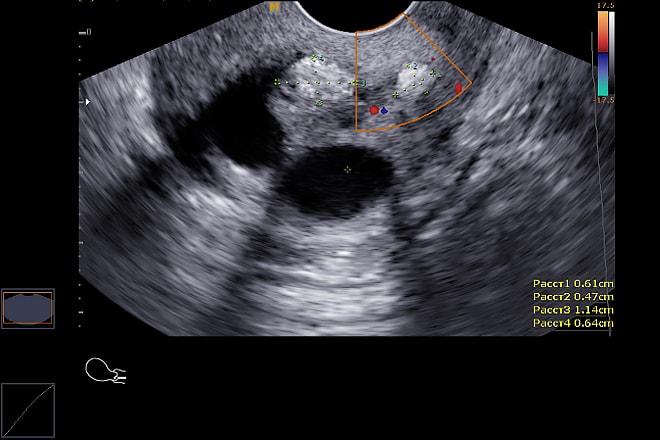

Гиперэхогенное образование представляет собой область с повышенной плотностью, которая хорошо видна при ультразвуковом исследовании. Для постановки точного диагноза врачу необходимо провести дополнительные обследования. Важно выполнить дифференциальную диагностику, чтобы исключить возможность злокачественных образований.

Эксперты в области гинекологии подчеркивают важность правильной диагностики гиперэхогенных образований в яичниках, так как они могут указывать на различные патологии. Гиперэхогенные образования могут быть как доброкачественными, так и злокачественными, поэтому их классификация и дальнейшее обследование имеют решающее значение. Врачам рекомендуется использовать ультразвуковую диагностику для определения характеристик образования, таких как размер, форма и структура. Дополнительные методы, такие как МРТ или КТ, могут быть необходимы для более детального анализа. Важно также учитывать клинические симптомы и анамнез пациентки, что поможет в постановке точного диагноза и выборе оптимальной тактики лечения. Эксперты акцентируют внимание на необходимости регулярных обследований, особенно для женщин в группе риска, чтобы своевременно выявить возможные осложнения.

Ультразвуковая диагностика: Ультразвуковое исследование (УЗИ) является основным методом диагностики гиперэхогенных образований. Специфические характеристики, такие как форма, размер и наличие дополнительных признаков (например, васкуляризация), помогают врачам отличить доброкачественные образования от злокачественных.

Ультразвуковое исследование злокачественной кисты яичников показывает крупные образования с неправильной формой. Стенки капсулы тонкие и бугристые, а сами образования могут содержать несколько перегородок. В некоторых случаях выявляются множественные папиллярные кисты яичников. Одним из типов таких образований являются стромально-клеточные опухоли. Размер новообразований обычно не превышает 20 см, они имеют овальную форму и гладкую, плотную оболочку.

Гиперэхогенность новообразования — это не единственный признак, указывающий на возможность рака яичников. Врач может также выявить злокачественную опухоль, которая по результатам обследования будет иметь следующие характеристики:

При проведении ультразвукового исследования (УЗИ) можно установить: